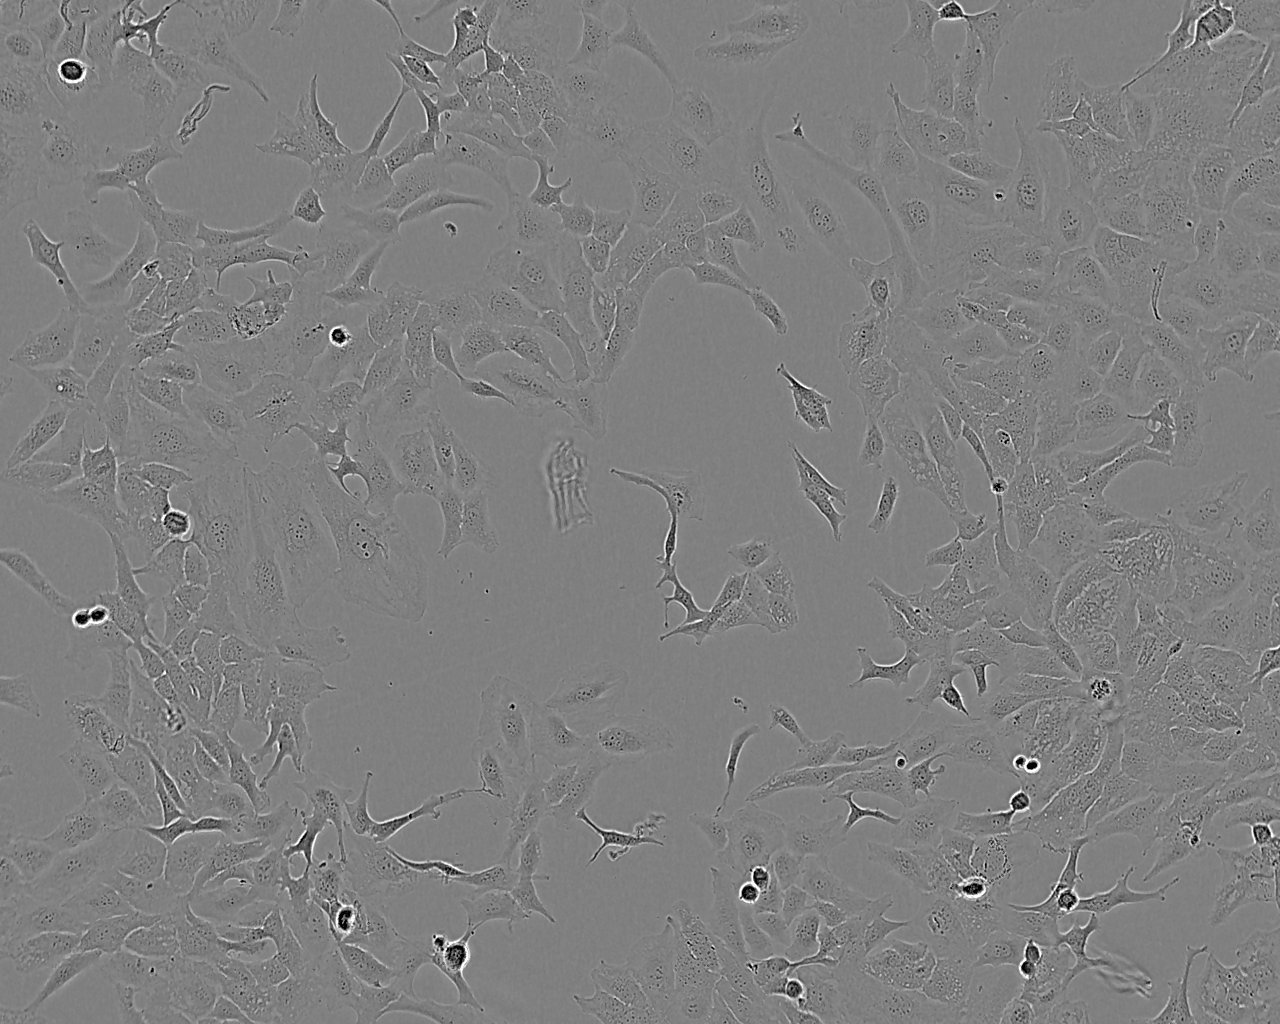

Images